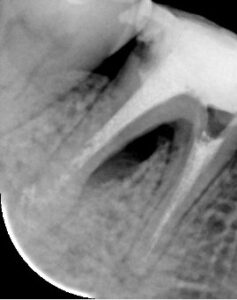

【分岐部に透過像がある】

【黄色囲み部分 分岐部透過像】

考察 根分岐部の透過像が歯周病由来であったのか根尖病巣由来であったのか判断できないケースであった。ただし通常の歯周根尖合併症は根管治療を適切に行えば治癒します。今回のケースは根分岐部のポケットと完全に交通しており、しかもそれが長期間放置されたと思われるので、根分岐部の骨欠損は歯周病の分岐部病変で骨を再生させる処置を必要としました。